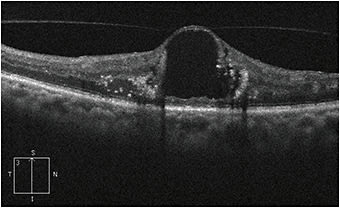

When evaluating these patients, ophthalmologists should use the clinical exam and optical coherence tomography (OCT). It is important to determine if the posterior hyaloid is separated completely (usually signaled by the presence of a Weiss ring) or if there is vitreomacular adhesion (VMA) and/or ERM. In cases where the status of the posterior hyaloid cannot be determined by exam and OCT, B-scan ultrasound may be helpful. Posterior vitreous separation happens in stages; many patients will have perifoveal separation with persistent adhesion at the fovea and disc. One challenge in evaluating patients is differentiating vitreous adhesion from vitreous traction. Focal distortion of the retinal contour at the site of adhesion is more suggestive of traction, as is a more perpendicular angle between the retina and posterior hyaloid (Figure 1). Patients with a flat posterior hyaloid attached to a cyst may be less likely to benefit from vitrectomy (Figure 2).

Figure 2: OCT of a patient with diabetic macular edema with a large central cyst and surrounding lipid. The posterior hyaloid is attached to the cyst; however there is no focal distortion of the retina at the site of adhesion, and the posterior hyaloid is oriented more tangential to the retina than in Figure 1. This appearance is less suggestive of a tractional component to DME and this patient may be less likely to benefit from pars plana vitrectomy.